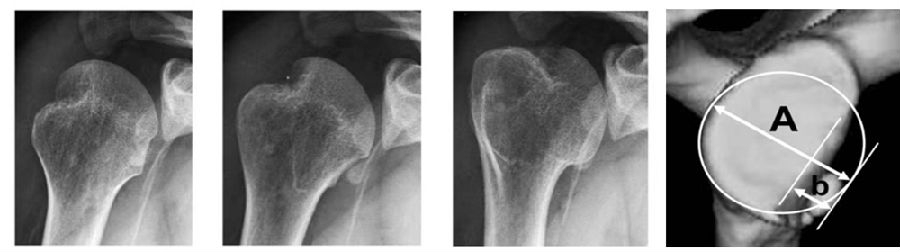

文献报道,伴有Hill-Sachs损伤概率达93%。肱骨头骨缺损(Hill-sachs损伤)的发生率占肩关节前向不稳病例的65%-93%。目前,肱骨头显著性骨缺损的评定标准尚无统一定论。Di Giacomo等将Hill-sachs损伤分为“On-track”和“Off-track”。

图8

当手臂上举时,肩胛盂与肱骨头的接触区域会从肱骨头的中下部向外上部分转移,这个相互的接触区域就被称为肩胛盂轨迹。接触区域的内侧缘到肩袖止点的内侧缘的距离约为84%肩胛盂的宽度。

图12

当没有肩胛盂骨缺损时,肩胛盂轨迹的宽度占了肩胛盂宽度的84%。当有肩胛盂前缘骨缺损时,应该从这84%的长度中减去骨缺损的宽度,这样才能够获得一个真正的肩胛盂轨迹的宽度。

上图显示接触区域的内侧缘到肩袖止点的内侧缘的距离约为83%肩胛盂的宽度。A1-B1是肩胛盂的长轴,C-D是肩胛盂的宽度,E-D是肩胛盂轨迹,为83%肩胛盂的宽度。B图为盂肱关节在外展外旋位的对合关系,肱骨头和肩胛盂接触区域内侧边缘(M)到肩袖足印区的内侧边缘(F)的距离,是肩胛盂宽度的83%±14%。(肩胛盂轨迹=F-M=83%肩胛盂的宽度)。